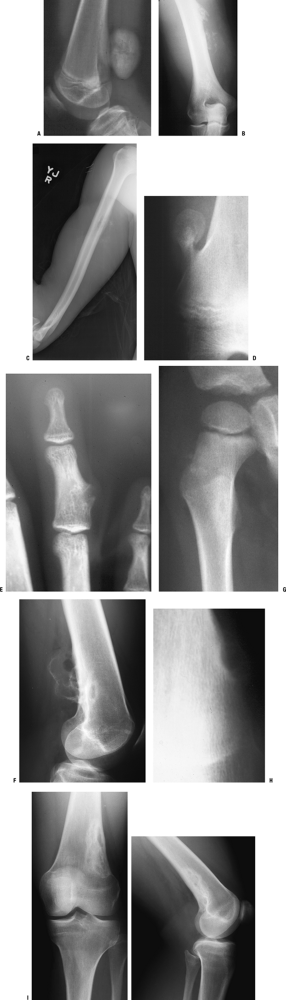

Figure 1-8 Common surface and intracortical eccentric bone lesions are displayed radiographically. (A) Parosteal osteosarcoma, (B) periosteal osteosarcoma, (C) high-grade surface osteosarcoma, (D) osteochondroma, (E) periosteal chondroma, (F) periosteal chondrosarcoma, (G) osteoid osteoma, (H) chondromyxoid fibroma, (I) nonossifying fibroma.Table 1.5 Types of Borders That Define Bone LesionsBorder Type of Transition Width of Transition Type of Bone Lesion Common Examples Geographic Narrow Pencil-thin line Latent benign vs. active Nonossifying fibroma (fibrous cortical defect)

Figure 1-9

Border types. The interface at the edge of any given bone lesion on

plain radiographs may be classified as geographic, moth-eaten, or

permeative. A geographic border, as illustrated by the proximal humeral

tumor on the left, has a very narrow zone of transition (able to be

traced with a pencil-thin line) between normal and abnormal bone and

usually represents an indolent benign process, such as a unicameral

bone cyst. A moth-eaten border, as illustrated by the distal femoral

tumor in the center, has a slightly blurred zone of transition

(typically a few millimeters) and may reflect a more active process,

such as a giant cell tumor of bone. A permeative border, as illustrated

by the proximal femoral diaphyseal tumor on the right, is typified by a

broad zone of transition (usually 1 cm or greater) and usually

represents a more aggressive process, such as a sarcoma or metastatic

carcinoma. These border types are only one piece of the radiographic

interpretation, and they cannot be relied upon wholly to determine

biologic activity.

Figure 1-10 Bone lesions with a spectrum of borders. (A) Nonossifying fibroma with a geographic border. (B) Fibrous dysplasia with a geographic to slightly moth-eaten border. (C) Giant cell tumor of bone with a moth-eaten border. (D) Lytic osteosarcoma with a permeative border.Table 1.6 Radiographic Types of Responses to Bone LesionsTypes of Response Definition Classic Examples Marginal sclerosis Dense peripheral medullary lamellar bone margin to inactive, active, or very slowly expansile aggressive lesions Nonossifying fibroma

Figure 1-12 Bone lesions with a spectrum of responses in the surrounding bone. (A) A proximal femoral fibrous dysplasia lesion shows marginal sclerosis. (B) A humeral diaphyseal region of cortical thickening is seen here in association with an area of chronic osteomyelitis. (C)

Poorly organized new bone formation demonstrating both Codman’s

triangle and a sunburst appearance is shown here in an osteosarcoma. (D) Periosteal neocortical response is seen in the posterior cortex of the distal tibia due to this aneurysmal bone cyst. (E) Onion-skinning periosteal reaction with Codman’s triangle and an associated soft tissue mass is shown in this Ewing sarcoma. (F) Endosteal expansion and erosions are seen with this low-grade chondrosarcoma.Table 1.7 Patterns of Mineralization Within Bone LesionsDescription Typical Lesions Other Distinguishing Features Radiolucent (lytic) Absence of matrix Numerous (nonspecific) Numerous Mineralized Calcified Punctate rings and arcs Hyaline cartilage lesions*

Figure 1-13 Bone lesions with a spectrum of types of matrix mineralization. (A) Absence of matrix mineralization is seen in a lucent lesion from a unicameral bone cyst. (B) The typical rings and arcs of hyaline cartilage matrix mineralization are seen in this metacarpal enchondroma. (C) The same type of hyaline cartilage matrix mineralization is apparent in this chondrosarcoma. (D) Ground glass appearance is typical of fibrous dysplasia, as in this lesion of the proximal radius. (E)

A mixed sclerotic and partially lytic lesion of the proximal femur,

which is frequently seen in the setting of metastatic breast cancer. (F) Densely sclerotic metastases are the most common appearance in bony metastatic prostate carcinoma. (G)

Lytic metastases are the most common appearance for metastatic lung

cancer, which is also the most common primary source for metastases

distal to the elbows and knees, as shown in this tarsal navicular

metastatic deposit from lung carcinoma. (H) A cumulus cloud pattern of matrix mineralization is most characteristic of osteosarcoma.Table 1.8 Multifocal Bone LesionsPediatrics Adults Metabolic bone diseases Multifocal Paget’s disease of bone Infections Chronic recurrent multifocal osteomyelitis Malignant neoplasms Metastases (neuroblastoma, rhabdomyosarcoma, osteosarcoma)